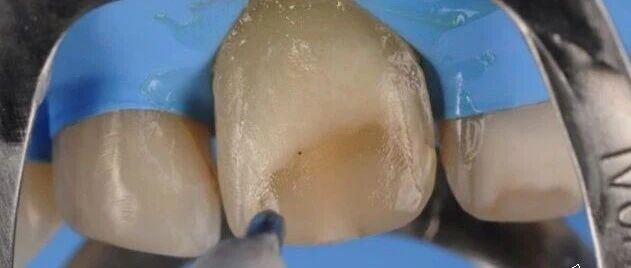

前牙唇面预备不足:前牙在制备过程中,切端的位置应制备与牙体长轴呈45°的斜面。如果不制备斜面无法保证足够的瓷层空间,修复体在恢复正常牙体形态时就无 法保证颜色,如果要保证颜色则修复体会唇倾,形态、弧度就会与邻牙不协调。为了修复体的最佳效果,所以唇侧的预备量一定要达到要求。

3.牙体制备完成有锐利的边缘

如切端的位置与各轴角相交的位置(点角和线角)。如果制备好的牙体存在锐角、锐边,导致的结果可能有:

①修复体无法完全就位,这些锐角、锐边会成为障碍点,因为基底冠的内表面的光滑连续的,不可能存在锐角、锐边,这是材料和设备所决定的,氧化锆车针最细的直径为1.0mm,手动氧化锆车针最细的为0.6mm。

②如果患者接受这样修复体,那么完成后的修复体,患者在使用过程中容易出现崩瓷的现象,因为这些锐角、锐边会产生应力集中。